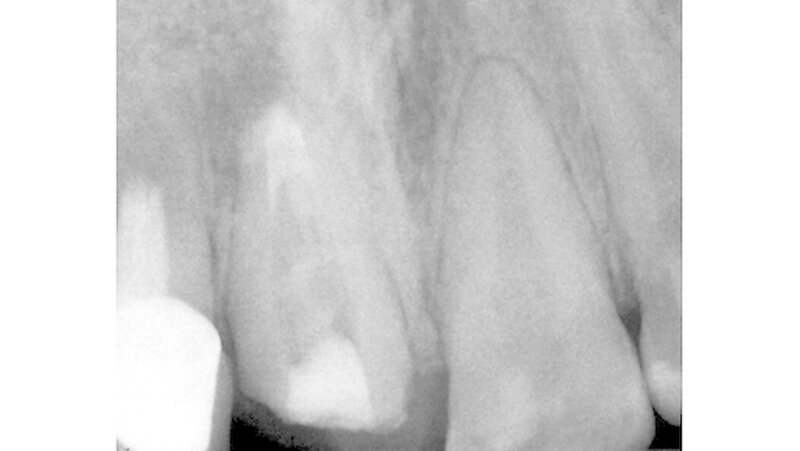

Im Verlauf der Behandlung wurden die prothetische Suprakonstruktion an 11 abgenommen und der Zahn retrepaniert. Durchgeführt wurden eine Revision der weitestgehend insuffizienten und überfüllten Wurzelkanalfüllung sowie eine zweiwöchige Kanaldesinfektion mit Kalziumhydroxid. Im apikalen Bereich wurde anschließend nach ausreichender manueller Aufbereitung in Circumferential Filing Technik sowie chemischer Desinfektion ein apikaler MTA-Plug (Mineral Trioxid Aggregat) eingebracht (Abbildung 3) und kondensiert. Es erfolgte eine röntgenologische Kontrolle des apikalen Verschlusses (Abbildung 4). Der Kanal wurde dann erneut provisorisch mit einer Kalziumhydroxidpaste versorgt und der Zahn mit Cavit verschlossen. Die Krone wurde mit Temp Bond rezementiert.

Am Folgetag erschien der Patient wieder zum Einbringen der definitiven Wurzelkanalfüllung. Die Krone wurde erneut abgenommen, die provisorische Füllung entfernt und der apikale Verschluss mikroskopisch kontrolliert. Nach wiederholter chemischer Desinfektion und abschließender Kanaltrocknung erfolgte die Guttapercha-basierte thermoplastische Wurzelkanalfüllung. Die Versorgung des Zahns mit Stiftaufbau und Krone wurde geplant, aber der Patient erschien nicht mehr zur weiteren Therapie.